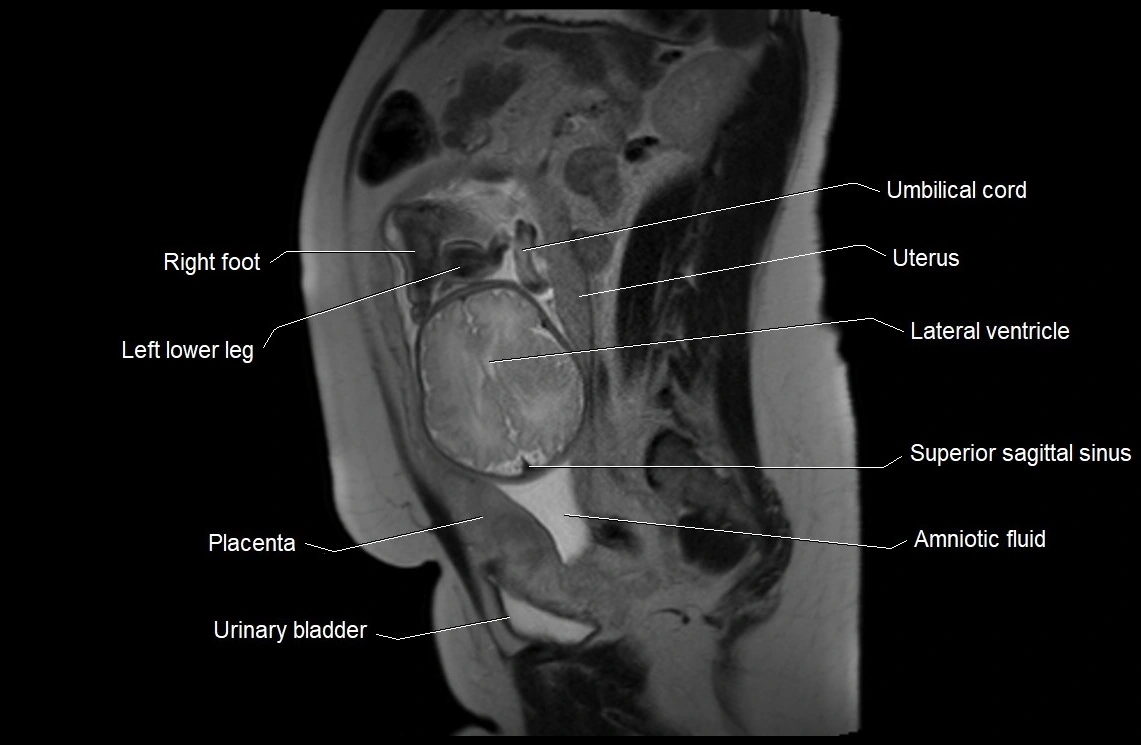

MRI Appearance

T2 HASTE (T2 GRE):

• Amniotic fluid shows very bright hyperintense signal

• Provides natural contrast against fetus and placenta

• Small particles (vernix) may appear as scattered hypointense foci within bright fluid